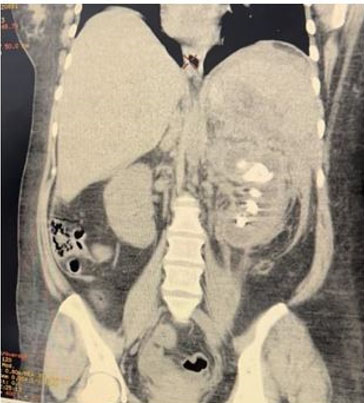

A 58-years-old Saudi male presented with two years history of right painless scrotal mass. There was no history of fever, genital trauma, genital infection, or tuberculosis (TB). The patient denied having nausea, vomiting, diarrhea, flushing, palpitations, or weight changes. On physical examination, the scrotum revealed a right-sided non-tender mass with 2 cm above and not attached to right testis. The left side of the scrotum was normal and no palpable lymph nodes. Normal tumor markers of testicular tumor. Ultrasonography revealed a well-defined, homogeneous, hyperechoic lesion measuring approximately 2 cm in the right extratesticular region.. It was seen superior to right testis and right epididymis and separable from them with high vascularity by Doppler study. Both testes appeared average in size and normal vascularity (Figure 1). Magnetic resonance imaging (MRI) with intravenous (IV) gadolinium contrast for abdominal and pelvis showed right extratesticular soft tissue mass not separable from the spermatic cord and there was no distant metastasis (Figure 2A, Figure 2B, Figure 2C). Based on images, provisional clinical diagnosis of a benign paratesticular mass was made and the patient underwent exploratory excision of the mass with preservation of cord and testis. The patient was discharged two days after surgery. Histopathology showed grossly a single soft gray light brown tissue mass measuring 2×2 cm with white firm focally fleshy cut surface. Microscopically, cells arranged in nested and trabecular growth pattern. The neoplasm is composed of tumor nests comprising of round cells with abundant granular eosinophilic-basophilic focally clear cytoplasm surrounded by sustentacular cells embedded in vascular rich stroma. The lesion exhibited no evidence of capsular invasion, lymphovascular invasion, a diffuse pattern, tumor necrosis, atypical mitosis, or increased mitotic activity. Histopathology reported this mass is paraganglioma.

Figure 1: Ultrasonography showed homogeneous hyperechoic lesion measuring approximately 2 cm.